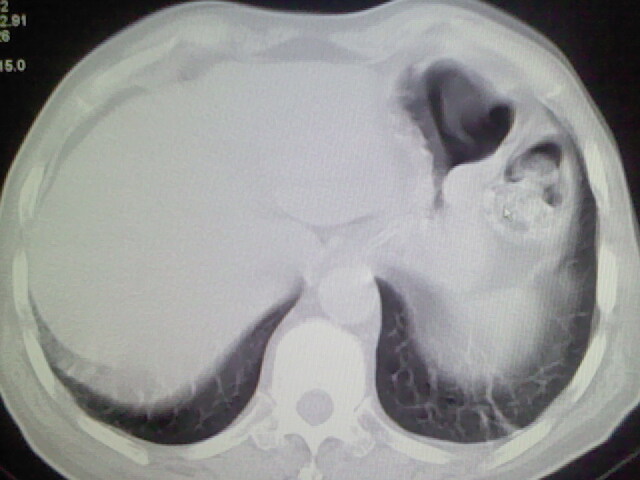

男,70岁,脑出血,长期卧床,左侧背部可触及肿块

考虑右肺及左肺下叶炎症。

右肺及左肺下叶炎症。

考虑右肺及左肺下叶慢性炎症。

肺部感染,背部筋膜增厚,考虑坠积性水肿或炎症

右侧肺部见片状密度增高影,边缘模糊。考虑炎症。另食管壁增厚。